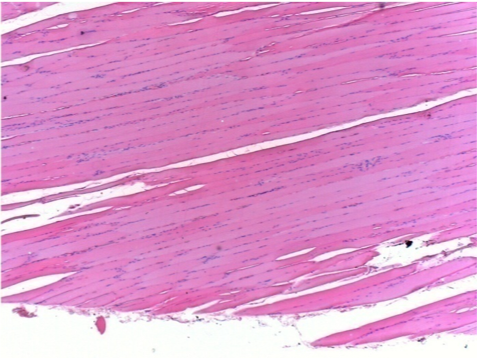

Через 1 місяць після ін'єкції Ендопілу 0,1 мл у правий претибіальний м'яз.

Те, що видно на знімках чорним кольором, не є некрозом, як можуть собі уявити деякі науковці!

Насправді, слід взяти до уваги 4 висновки